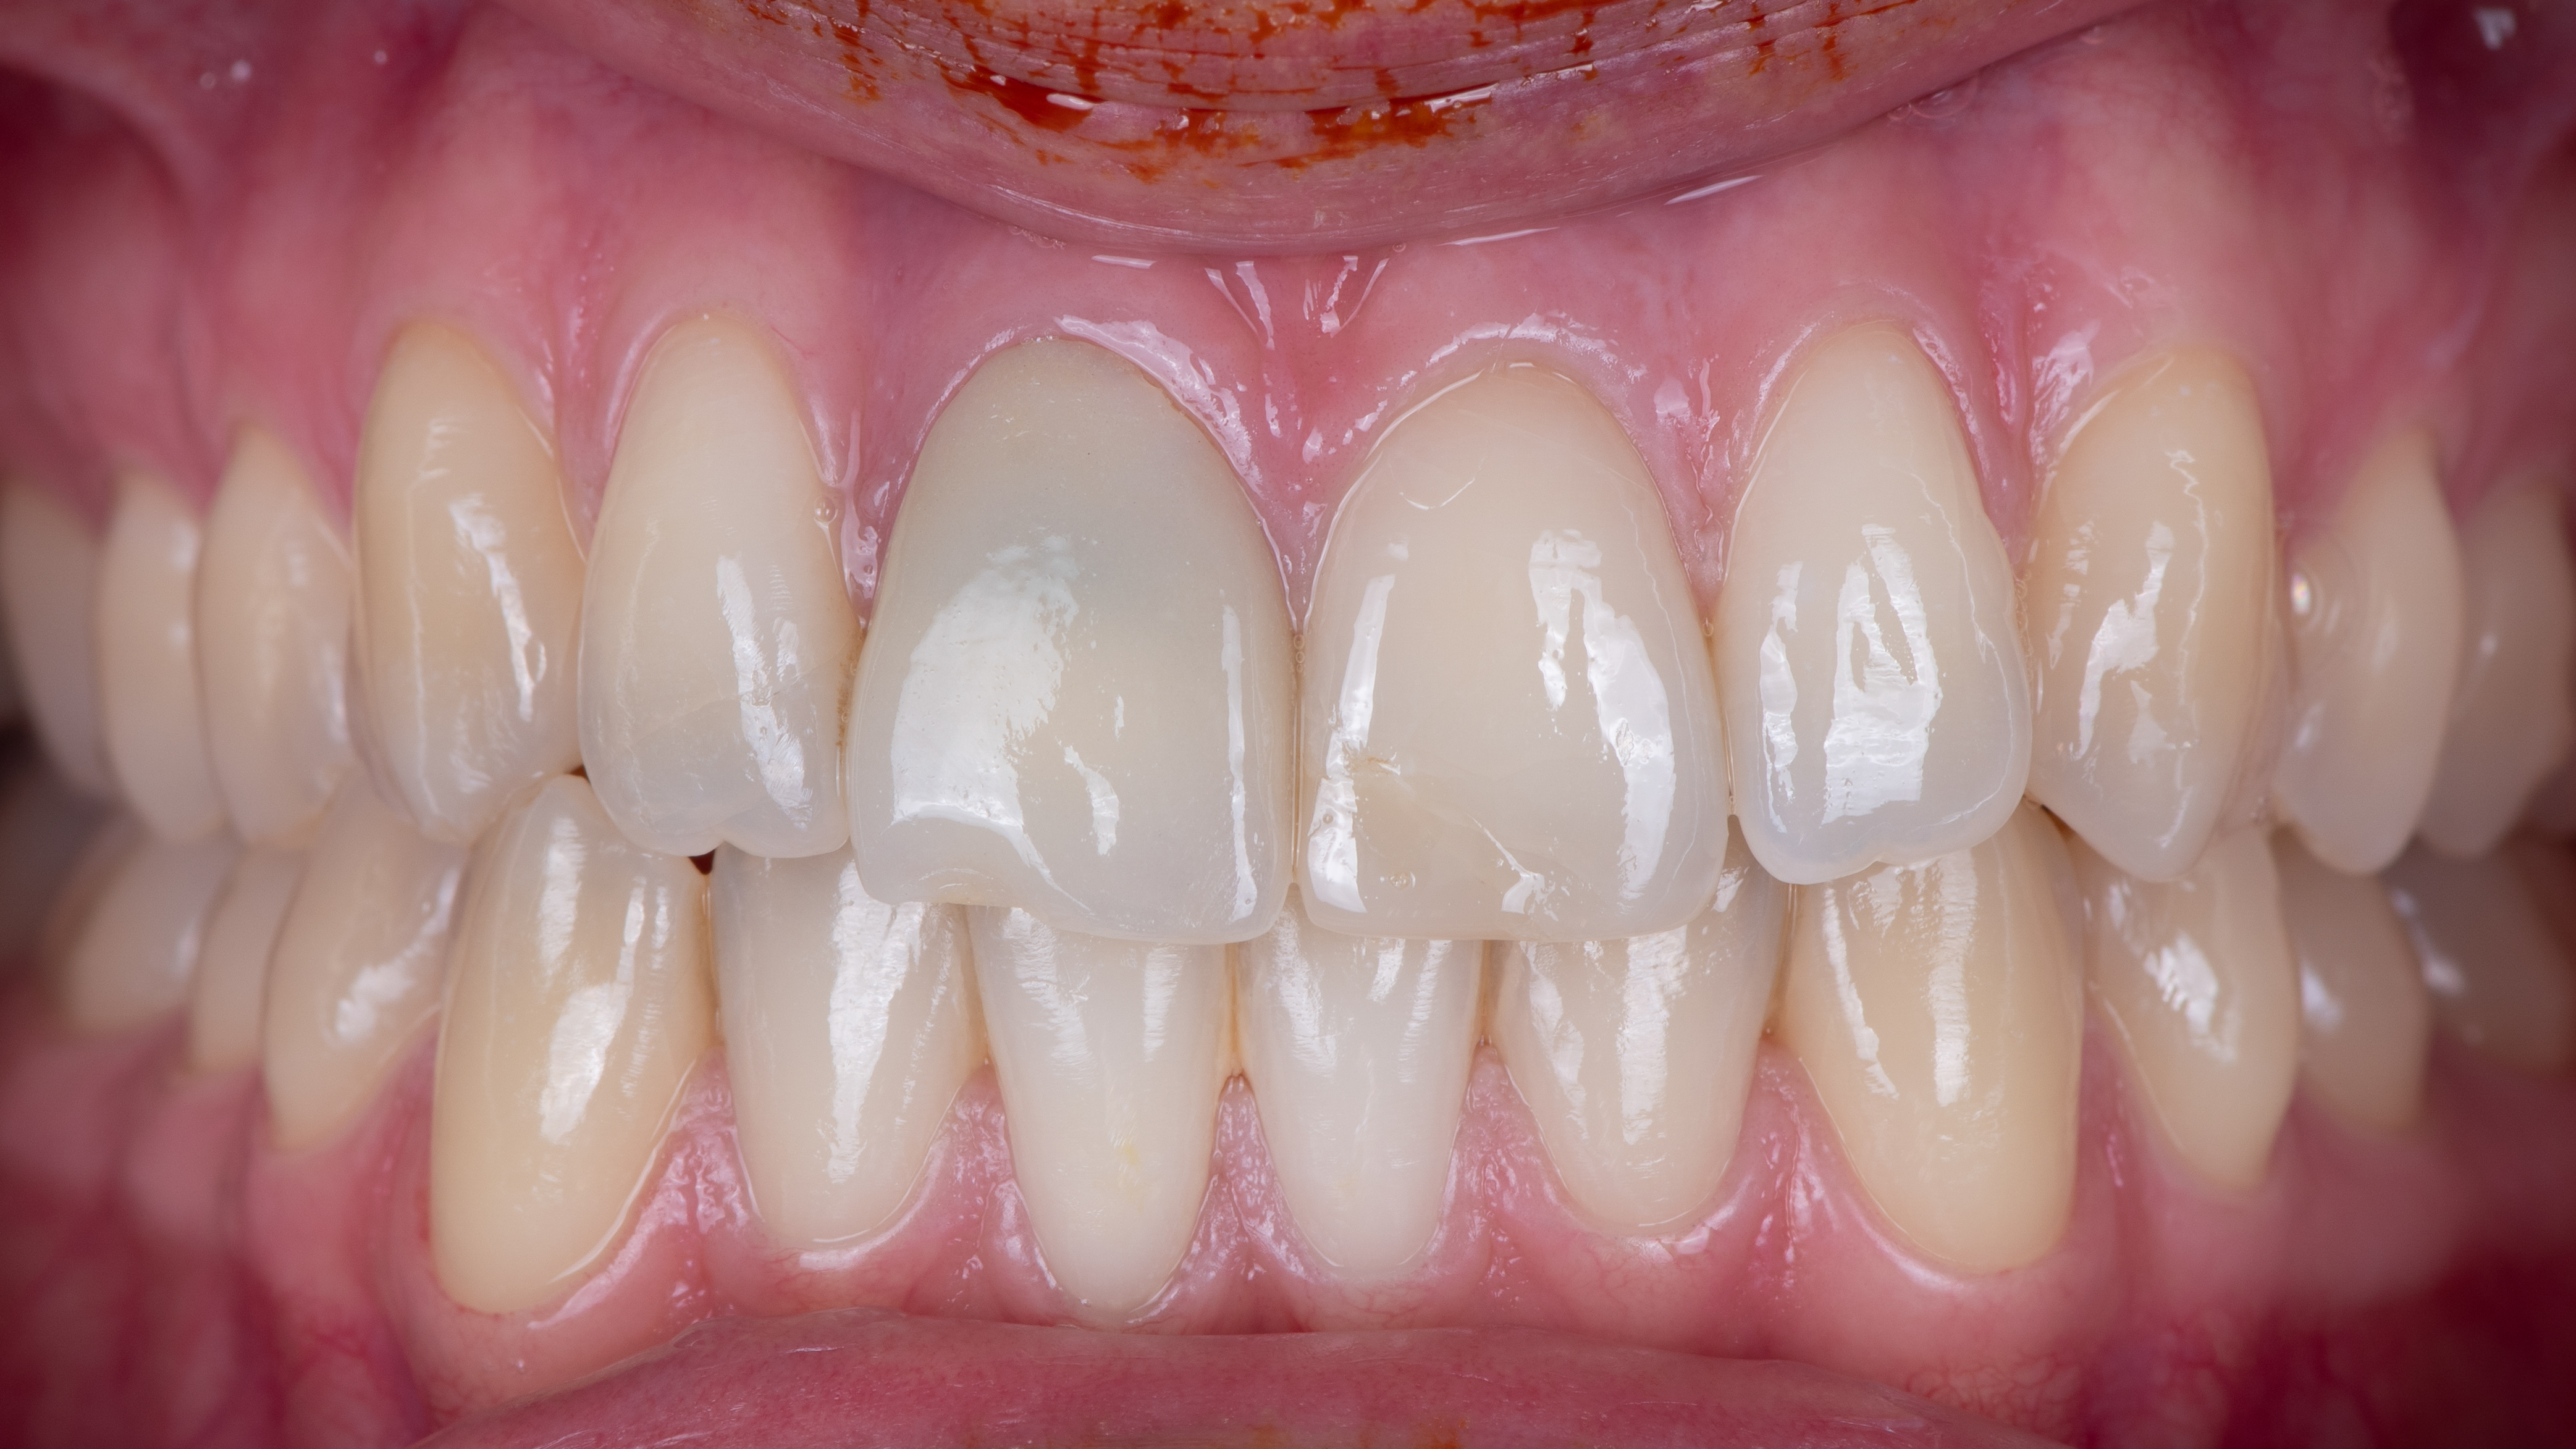

Nous constatons que la cicatrisation est alors optimale et que la prothèse d’usage s’intègre parfaitement à son environnement (Photo 20).

Intégration des réhabilitations au niveau du sourire de la patiente (Photo 26).